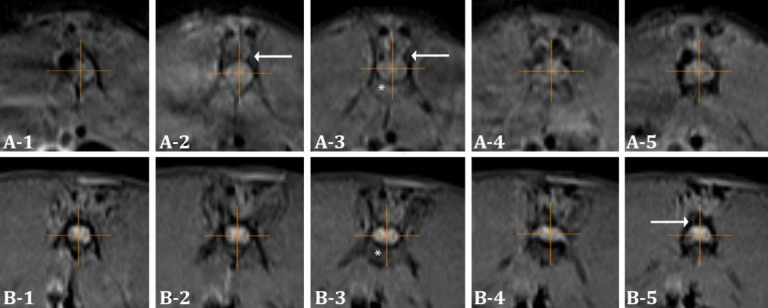

Significant advancements in imaging and surgical methodologies have led to more frequent performance of neurosurgical procedures such as laminectomy in both animal and human patients. Epidural fibrosis (EF) is defined as the excessive formation of scar tissue in the epidural space after lumbar laminectomy, often resulting in recurring postoperative pain. Given the association between postoperative hematoma accumulation at the laminectomy site and the development of EF, the present study aimed to evaluate the preventive impact of tranexamic acid (TXA), an antifibrinolytic agent with well-recognized hemostatic properties across various surgical fields. A rabbit laminectomy model was constructed to assess its effectiveness in reducing EF formation. A total number of 18 adult New Zealand White male rabbits were randomly divided into two groups: The control (saline) group and the treatment (topical TXA) group. Each rabbit underwent a two-level laminectomy at L3-L4. The treatment group received 5.00 mL of 100 mg mL-1 TXA solution applied topically to the laminectomy site, while the control group received 5.00 mL of saline. Postoperative evaluations included magnetic resonance imaging at week six to assess EF, followed by histopathological examinations to evaluate fibroblast cell density in scar tissue, EF grading and thickness of the dura mater. The analysis of magnetic resonance imaging and histopathologic data revealed significant differences between the two groups indicating that topical administration of TXA might be a promising approach for preventing EF.